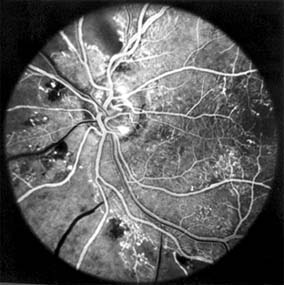

Figure 15-19: Diabetic retinopathy. Fluorescein angiogram shows florid retinopathy of diabetes with extensive areas of capillary closure, dilated capillaries with microaneurysms, and early new vessel formation at the optic disk.

Figure 15-20: Proliferative diabetic retinopathy. Fluorescein angiogram shows extensive growth of vessels into the vitreous with marked fluorescein leakage.